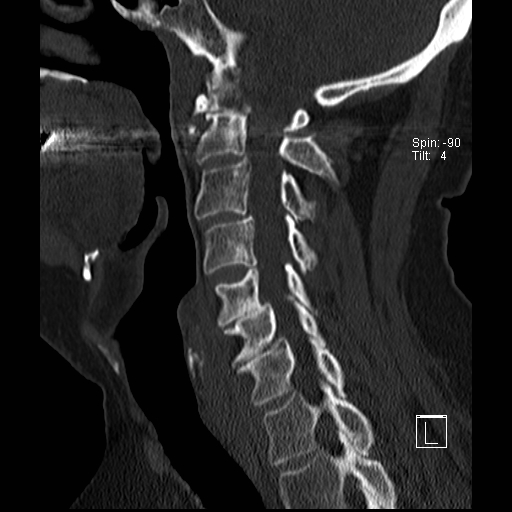

Lồng nền sọ

Lồng nền sọ, còn gọi là sụt lún sọ não hay ấn nền sọ, xảy ra ở 5-10% bệnh nhân viêm khớp dạng thấp cột sống cổ.

Trong lồng nền sọ, mỏm răng sa vào lỗ chẩm làm thu hẹp không gian dành cho tủy sống.

Biểu hiện lâm sàng đa dạng, từ đau đầu mạn tính, hạn chế vận động cổ đến suy giảm thần kinh cấp tính (chèn ép tủy sống và thân não, có thể dẫn đến liệt hoặc thậm chí tử vong nếu cổ bị di chuyển ở một số tư thế nhất định).

Hình ảnh

Cuộn xem các lát cắt CT.

Có hình ảnh di chuyển lên trên của mỏm răng vào lỗ chẩm.